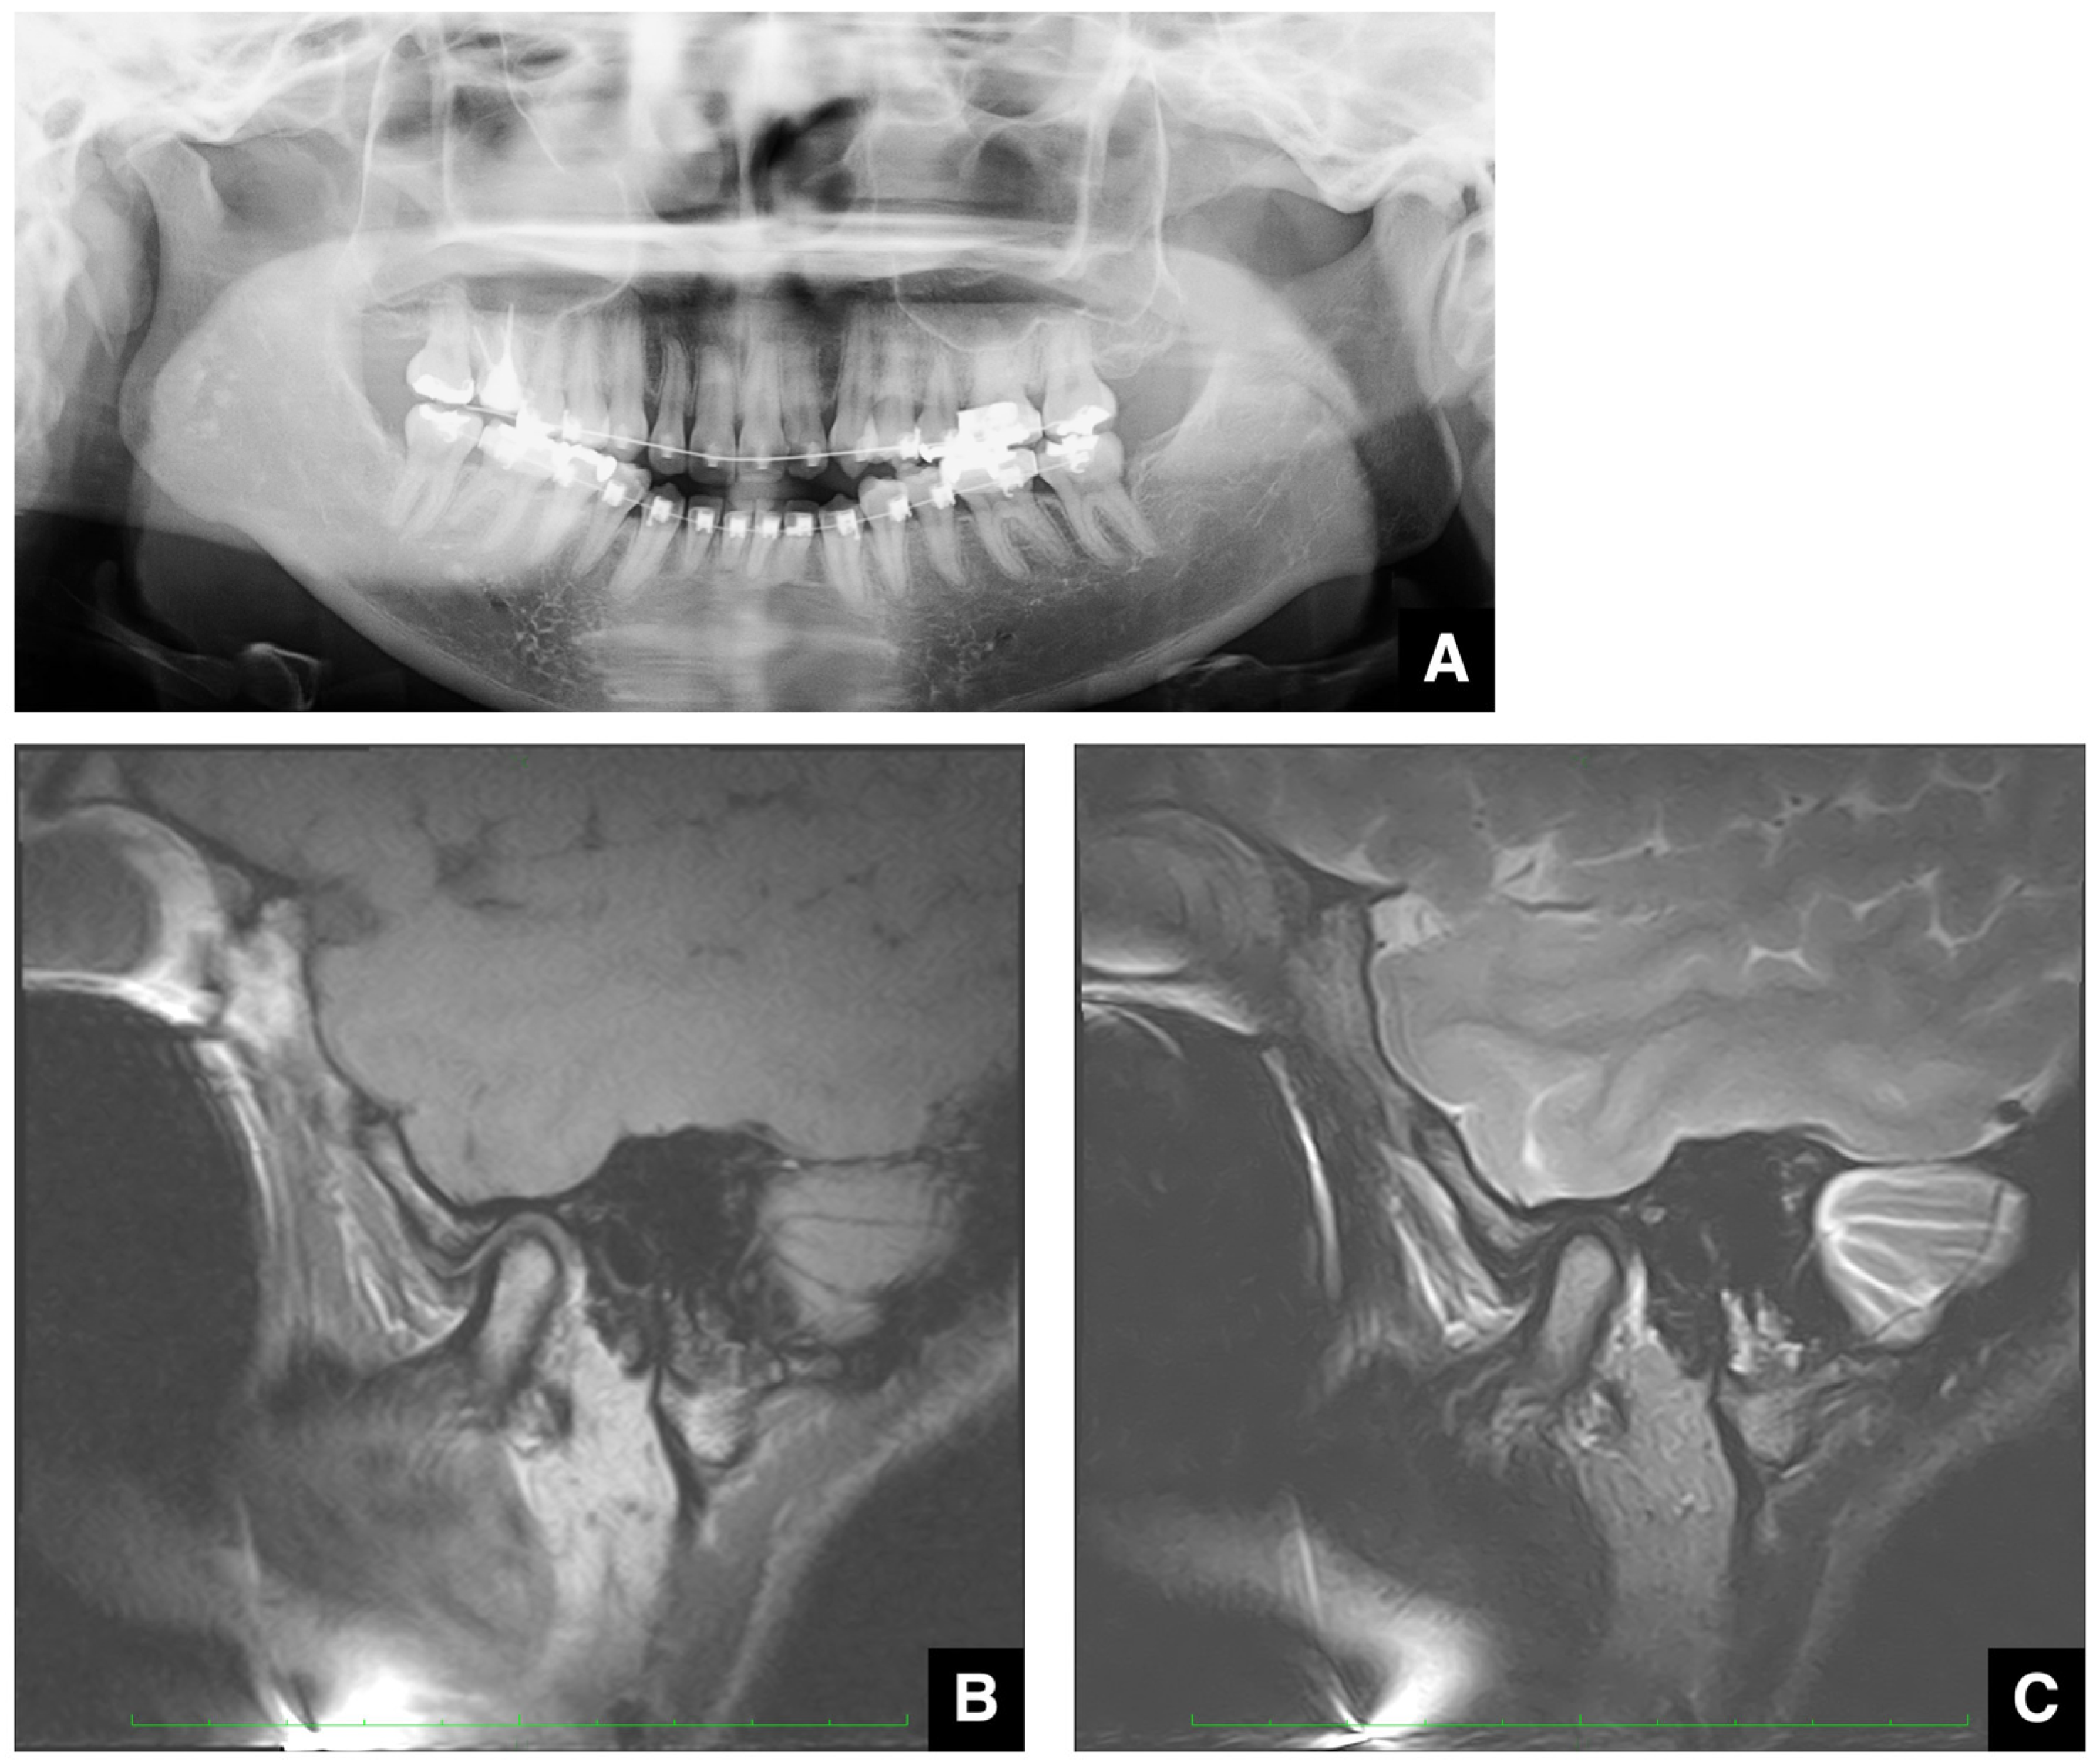

| Improving safety through prediction of surgical difficulty and complication 1. Circumstance of pterygoid venous plexus Carefully observe the fat tissue surrounding the medial and lateral pterygoid muscles to assess the development of the internal vascular structures (using CT and MR to evaluate the size of the fat tissue) 2. Fusion status of the maxillary tuberosity and pterygomaxillary suture When the fusion is narrow and the degree of calcification (CT number) is low or when the fusion is wide and high 3. Course of the descending palatine artery and thickness of surrounding bone When the palatal canal wall is thick, the probability of damage during transection is low. When it is thin, the possibility of damage cannot be ruled out. Setting the osteotomy line 1. Distance from the piriform rim to the greater palatine canal Long, short, cortical bone thickness, presence or absence of bone irregularities 2. Evaluation of the size, morphology, and internal features (mucosa, septa, etc.) of the maxillary sinus Size, shape, presence or absence of septa, presence or absence of masses, presence or absence of mucosal thickening 3. Relationship between the floor of the maxillary sinus and the apices of the molars Describe the maxillary sinus floor and the apex of each molar tooth 4. Presence of nasal septal deviation, size of the nasal passages, and thickness of the lateral nasal wall bone Presence or absence of nasal septal deviation, Size of the nasal passage, Thickness of the cortical bone of the lateral wall 5. Course of the mandibular artery The course from the pterygoid cleft to the pterygopalatine fossa in the posterior maxilla |